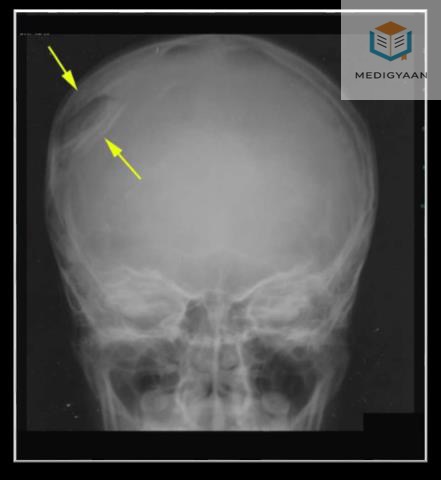

Question Image